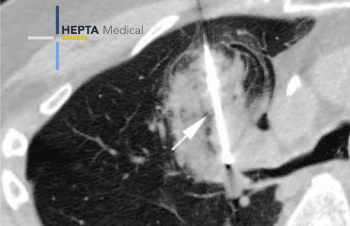

Capital innovation

Hepta Medical chauffe avec de nouveaux VCs